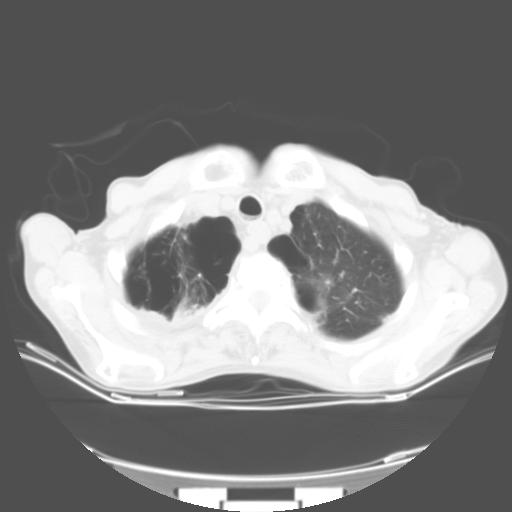

来院做头颅+胸部ct平扫

遂加作增强:

胸部病变平扫35hu,增强强化至70hu

这个病人首先是胸部病变的定位到底是肺内还是肺外。仔细观察块影位于胸膜下,与胸膜间有透亮带,且近端血管未见明显推移而是引流样改变,形态分叶,说明这个病灶位于肺内胸膜下。很可能是腺癌,腺癌最易致颅内高密度转移灶。局部胸膜有侵犯。

本例颅内见多发大小不等高密度灶,有强化及水肿;另外,胸锁关节层面可能是第四胸椎及右侧肋骨起始部骨质欠连续,椎旁软组织肿胀,建议调骨窗观察。

基于以上原因,所以炎性肿块或胸膜间皮瘤不考虑。

诊断:右下肺癌伴颅内、胸椎、肋骨转移可能性最大。

8楼版主所提的问题横好:此病例的讨论焦点应该是\"病灶的位置\".我认为其实质是“局限性胸膜间皮瘤与肺内肿块的鉴别诊断!”

我的诊断意见:肺内占位”病灶。片内骨质未见异常。

建议楼主提供强化的肺窗及双窗位图象{病灶边缘血管和支气管是否在病灶边缘突然中断换进入病灶内,如有可提示是肺内灶,如周围血管支气管有移位可提示是肺外病灶,如胸膜间皮瘤。胸膜间皮瘤的胸膜外脂肪层一般较清晰}。